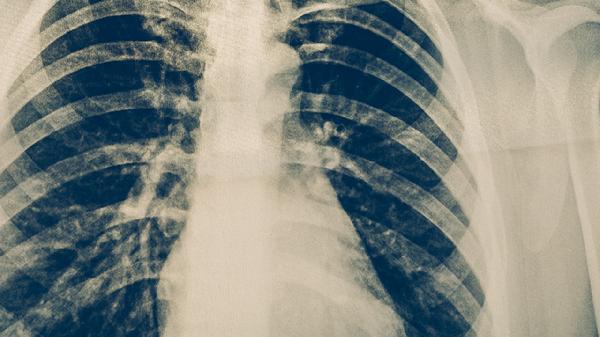

肺结核患者除注意饮食外,需保证每日充足睡眠,避免过度劳累。居住环境应通风良好,阳光照射。按医嘱规范服用异烟肼片、利福平胶囊、吡嗪酰胺片等抗结核药物,不可自行停药。定期复查胸部X线及肝肾功能,出现食欲明显下降或药物不良反应时及时就医。保持乐观心态,适当进行散步等低强度运动有助于康复。